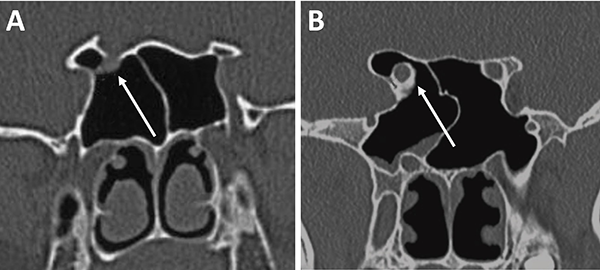

En referencia a las variantes turbinales se debe considerar la presencia de hipertrofia turbinal inferior y de cornetes medios bullosos (fig. 10). Ante la hipertrofia turbinal inferior será necesario realizar buena vasoconstricción preoperatoria asociada a luxofractura y lateralización para lograr un abordaje adecuado si es que no se asocia un tratamiento para la insuficiencia ventilatoria. Los cornetes medios bullosos representan una variante hipertrófica con neumatización de los mismos, los cuales podrán resecarse parcial o totalmente para lograr el correcto abordaje.

Figura 10: Variantes turbinales en TC cortes coronales. A) Hipertrofia turbinal inferior (asteriscos blancos); B) Cornetes medios bullosos (asteriscos blancos) y desvío septal-espolón (flecha blanca).